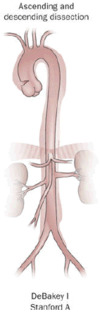

DeBakey

The DeBakey system, named after cardiothoracic surgeon Michael E. DeBakey, is an anatomical description of the aortic dissection. It categorizes the dissection based on where the original intimal tear is located and the extent of the dissection (localized to either the ascending aorta or descending aorta or involves both the ascending and descending aorta.[26]

• Type I – originates in ascending aorta, and propagates at least to the aortic arch and often beyond it distally. It is most often seen in patients less than 65 years of age and is the most lethal form of the disease.

• Type II – originates in the ascending aorta and is confined to it.

• Type III – originates in the descending aorta and rarely extends proximally, but will extend distally. It most often occurs in elderly patients with atherosclerosis and hypertension.

Stanford

The Stanford classification is divided into two groups, A and B, depending on whether the ascending aorta is involved.[27]

• A – involves the ascending aorta and/or aortic arch, and possibly the descending aorta. The tear can originate in the ascending aorta, the aortic arch, or more rarely, in the descending aorta. It includes DeBakey types I and II.

• B – involves the descending aorta or the arch (distal to the left subclavian artery), without the involvement of the ascending aorta. It includes DeBakey type III.

The Stanford classification is useful as it follows clinical practice, as type A ascending aortic dissections generally require primary surgical treatment, whereas type B dissections generally are treated medically as initial treatment with surgery reserved for any complications.